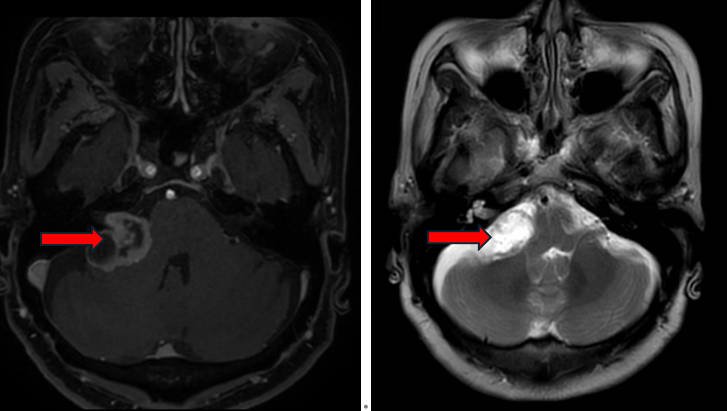

MRI(红色箭头所指为听神经瘤):

T1加权像上略低或等信号,T2加权像上高信号